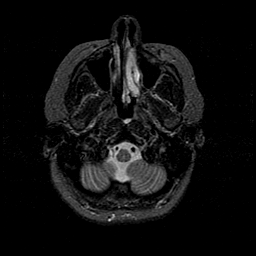

MR Study #1 -- Slice #9

[Home][Help][Clinical][Tour 1][Tour 2][Tour 3] Slice 9